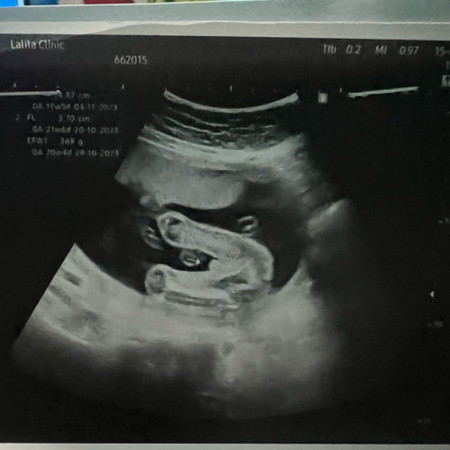

รบกวนช่วยดูทีค่ะ

หมอที่ซาวด์บอก ช หมอที่ฝากครรภ์บอกไม่แน่

ชายจ้า